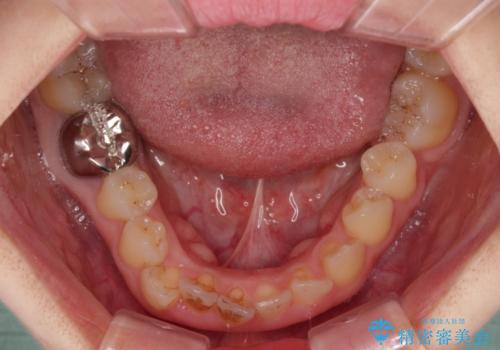

- 前歯のデコボコと、着色が著しい保険診療の前歯クラウンを気にして来院された患者様です。

左上の犬歯が埋伏しており、CT画像より萌出は困難と判断されたため、残存している歯にて歯列と咬合を整えることとしました。

マウスピース装着は煩わしいとのことで、表側のワイヤー装置にて矯正治療を行うこととしました。